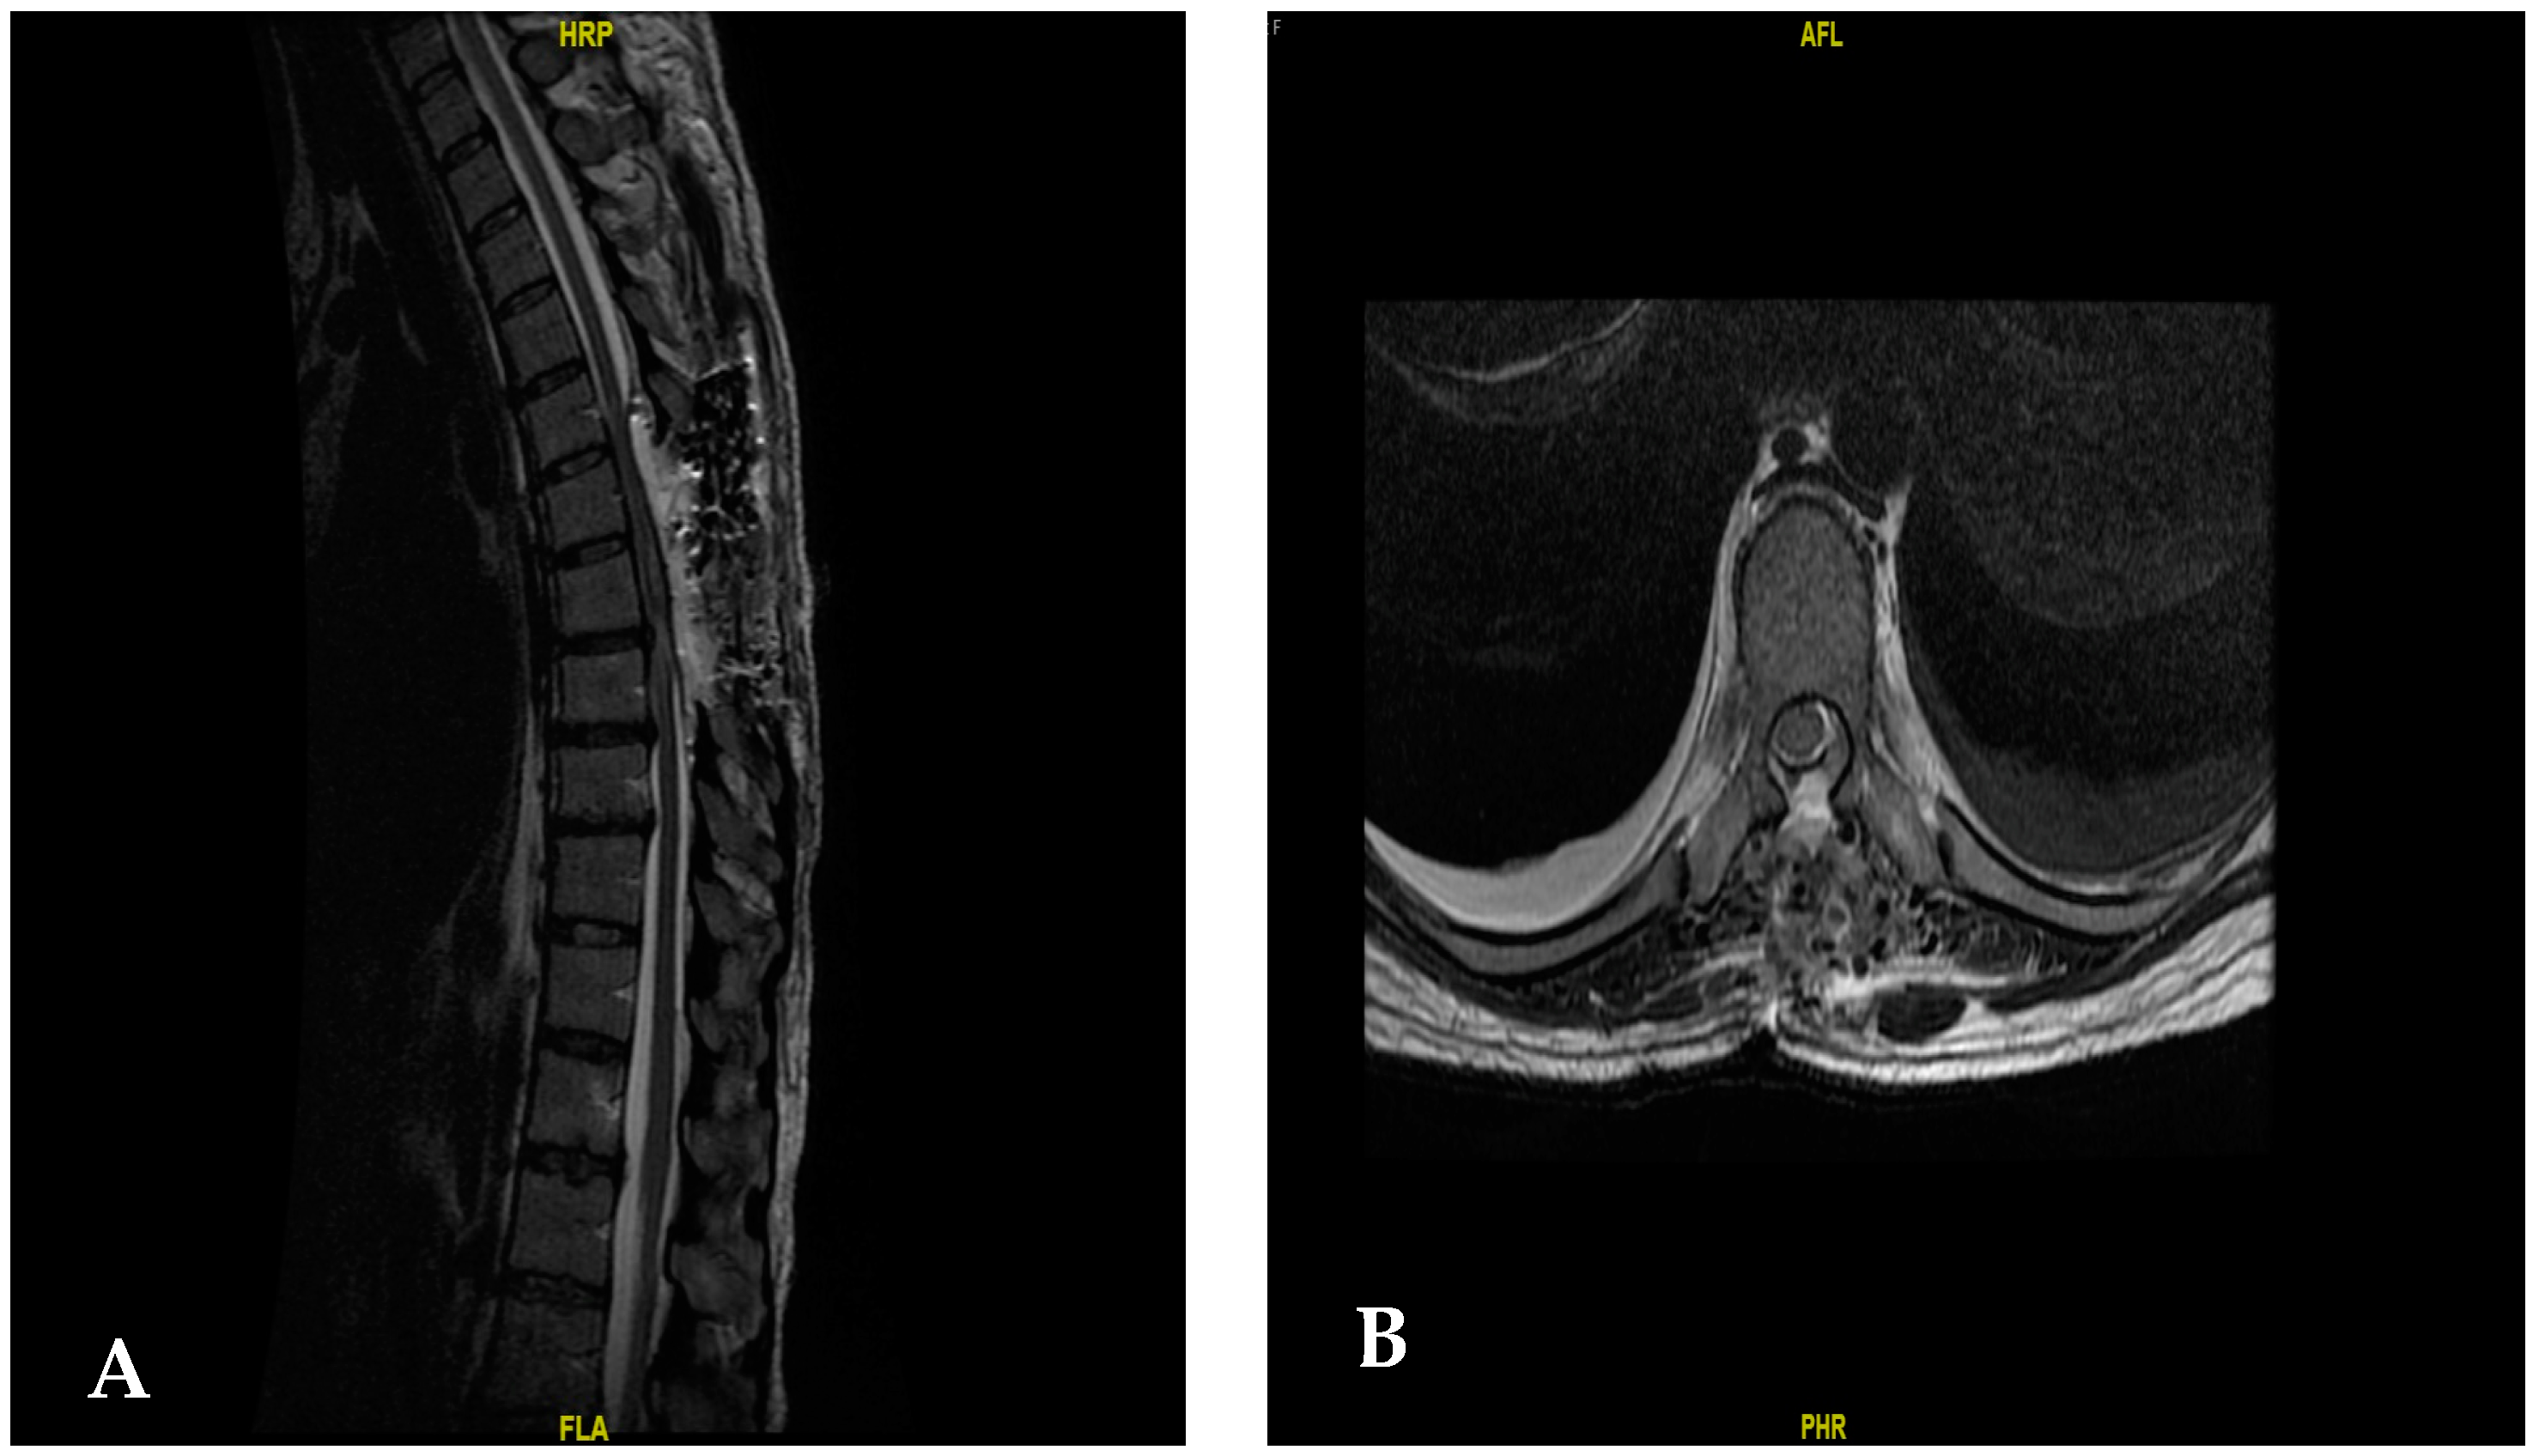

A 3-level laminectomy was performed from T6 to T8 using the Medtronic Midas Rex drill and a 5 mm diamond drill with microsurgical resection of the lesion (5 June 2023). During the procedure, there was a failure of the microscope light, and so the total resection of the tumor was not performed. However, there was a partial improvement in symptoms, with an increased strengthening of both limbs. A new MRI was ordered three days after the first surgical intervention performed on 8 June 2023, showing a residual tumor towards the rostral and cephalic levels (Figure 2).

Figure 2.

(A) The MRI results after the first surgical intervention. It shows the distal part of the tumor that was resected, with the proximal part missing, which still causes the compression on the dural sac. (B) Magnetic resonance image of the axial section after the first surgery.